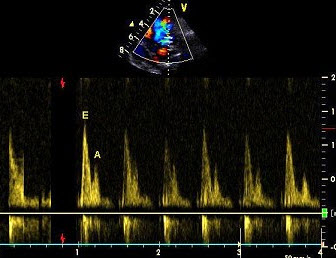

90、单项选择题

患者、男性,69岁,胸闷呼吸困难,心电图提示心梗,彩色多谱勒二尖瓣舒张期血流速度提示()

A.左室顺应性下降

B.左室顺应性正常

C.左室舒张功能假性正常化

D.以上都不是

E.二尖瓣狭窄